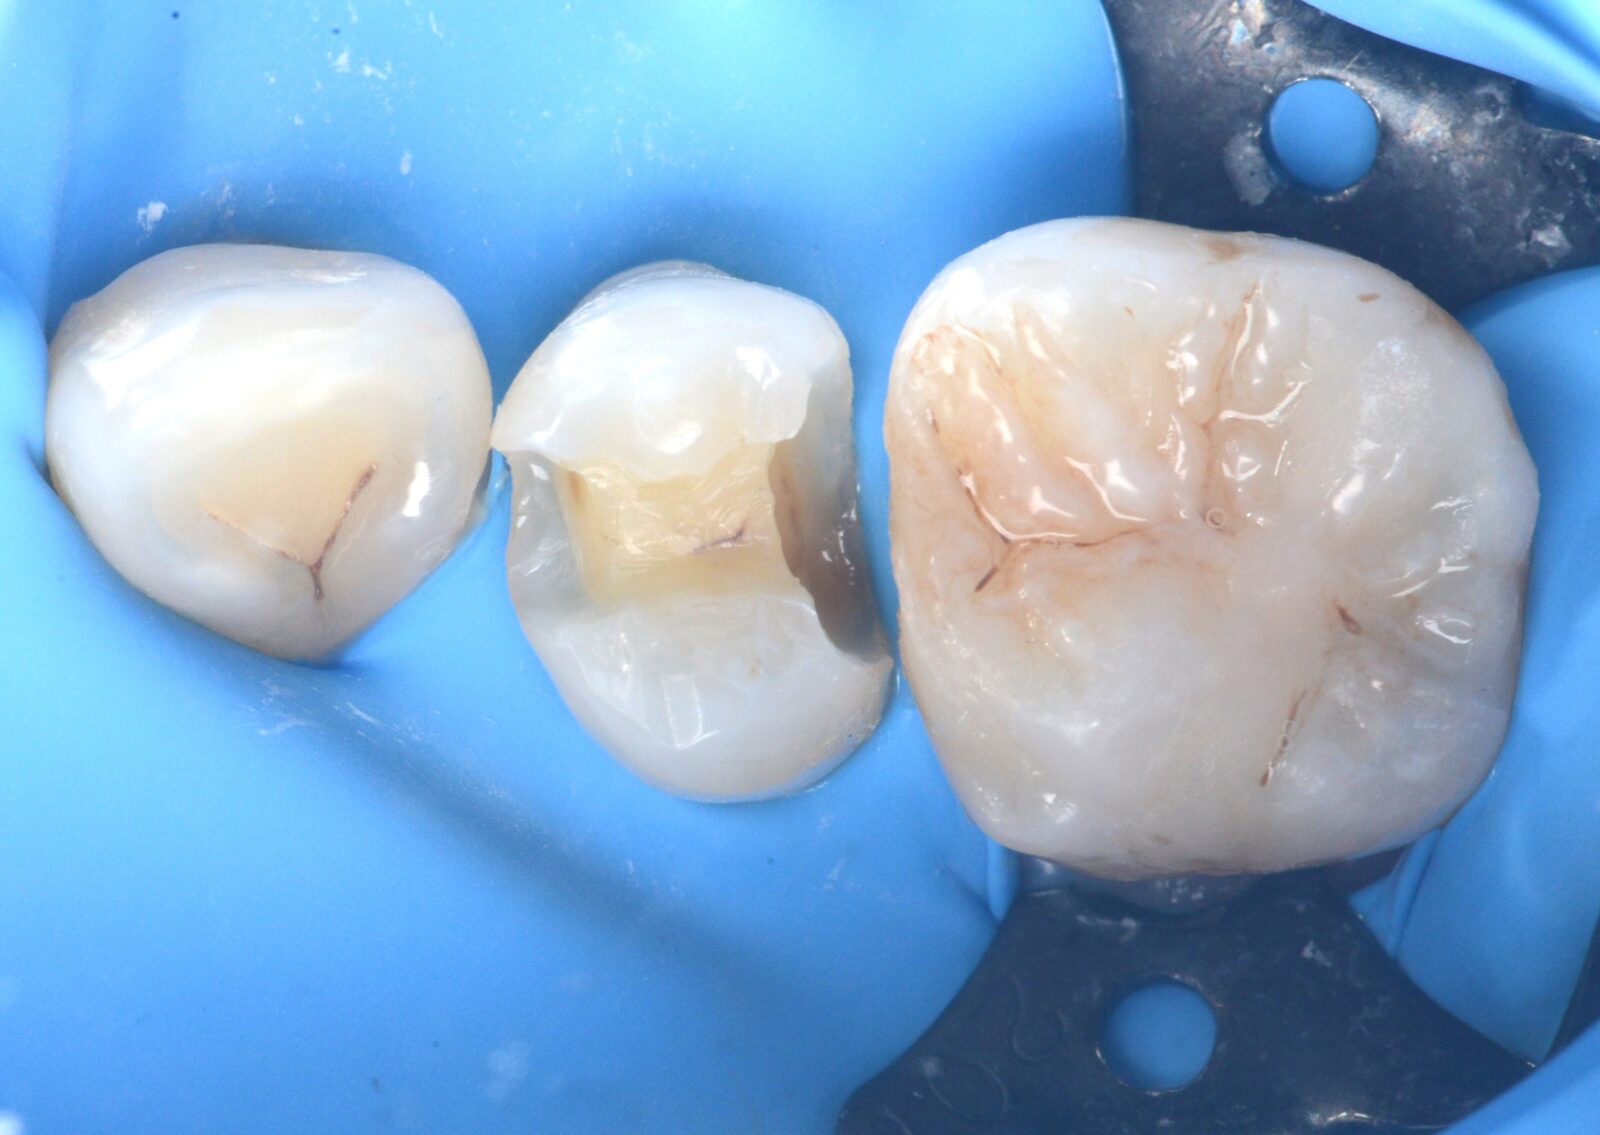

治療前 治療後

右下7ダイレクトボンディング

虫歯の治療希望で、右下の旧充填物と感染歯質の除去。 ラバーダム下で、プラークアウトと歯面処理を行い、接着操作とレジン充填を行った。 咬合調整はほぼなく研磨で終了。